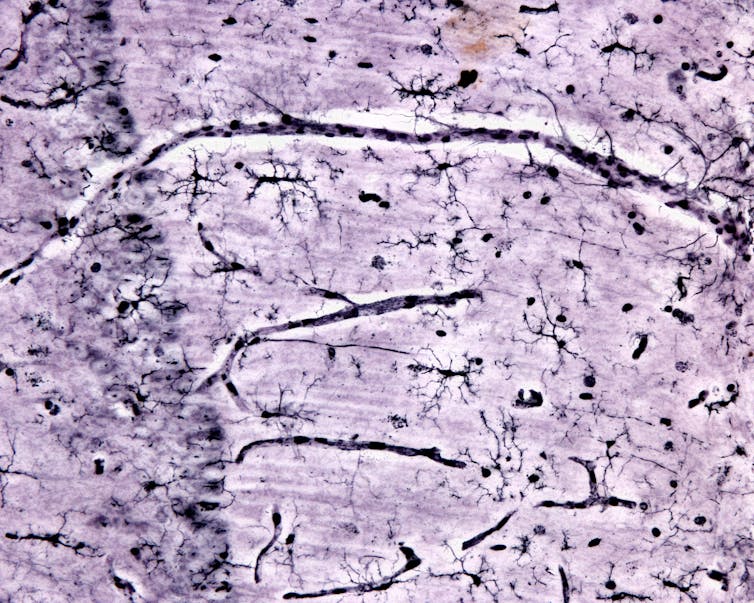

Microglia are immune cells masquerading as brain cells. In mice, microglia originate in the yolk sac of an embryo and then infiltrate the brain early in development. The origins and migration of microglia in people are still under study.

Microglia play important roles in healthy brain function. Like other immune cells, microglia respond rapidly to pathogens and damage. They help to clear injuries and mend afflicted tissue, and can also take an active role in fighting pathogens. Microglia can also regulate brain inflammation, a normal part of the immune response that can cause swelling and damage if left unchecked.

Microglia also support the health of other brain cells. For instance, they can release molecules that promote resilience, such as the protein BDNF, which is known to be beneficial for neuron survival and function.

But the keystone feature of microglia are their astounding janitorial skills. Of all brain cell types, microglia possess an exquisite ability to clean up gunk in the brain, including the damaged myelin in multiple sclerosis, pieces of dead cells and amyloid beta, a toxic protein that is a hallmark of Alzheimer’s. They accomplish this by consuming and breaking down debris in their environment, effectively eating up the garbage surrounding them and their neighboring cells.

Given the many essential roles microglia serve to maintain brain function, these cells may possess the capacity to address multiple arms of neurodegeneration-related dysfunction. Moreover, as lifelong residents of the brain, microglia are already educated in the best practices of brain protection. These factors put microglia in the perfect position for researchers to leverage their inherent abilities to protect against neurodegeneration.